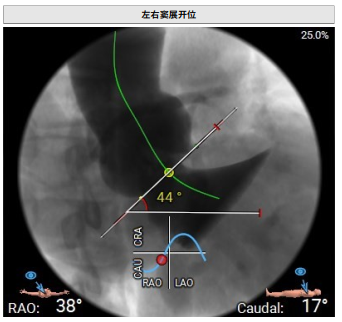

术中回顾及效果

在DSA与超声引导下,手术团队高效精准地完成了瓣膜的定位、释放与功能评估。手术过程顺利,夹持件入窦与定位一气呵成,三枚夹持件的释放与锚定位置与术前评估完全一致,器械用时仅6min左右。患者主动脉瓣重度反流纠正,术后无反流、无瓣周漏。术后心脏彩超显示人工生物瓣启闭良好,平均跨瓣压差3mmHg,流速正常,舒张压从30mmHg提升至70mmHg。